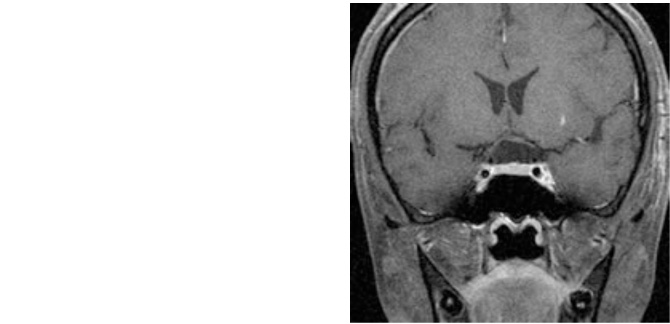

症例1は急激に進行する視力障害で来院された44歳女性です。視野検査で両目の外側が見えにくい両耳側半盲、右視力1.0、左視力は0.5と低下していました。両側の前頭葉の間から腫瘍を摘出し、視力は術後右1.5、左0.9、視野も改善しました。

図1:視神経を圧迫し視力・視野障害で来院。

術後MRI:腫瘍は摘出され視力も改善し退院。

嗅覚障害出現したが軽快しつつある。